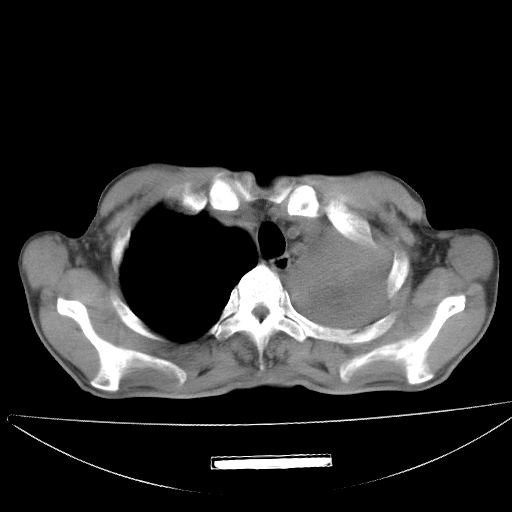

以下是引用杀毒软件在2009-4-28 17:58:00的发言:[br]考虑----左肺慢性肺脓肿形成继发上叶含气不良---抗炎后复查---待排肿瘤所致[br][br][本贴已被 杀毒软件 于 2009-4-28 18:01:26 修改过]